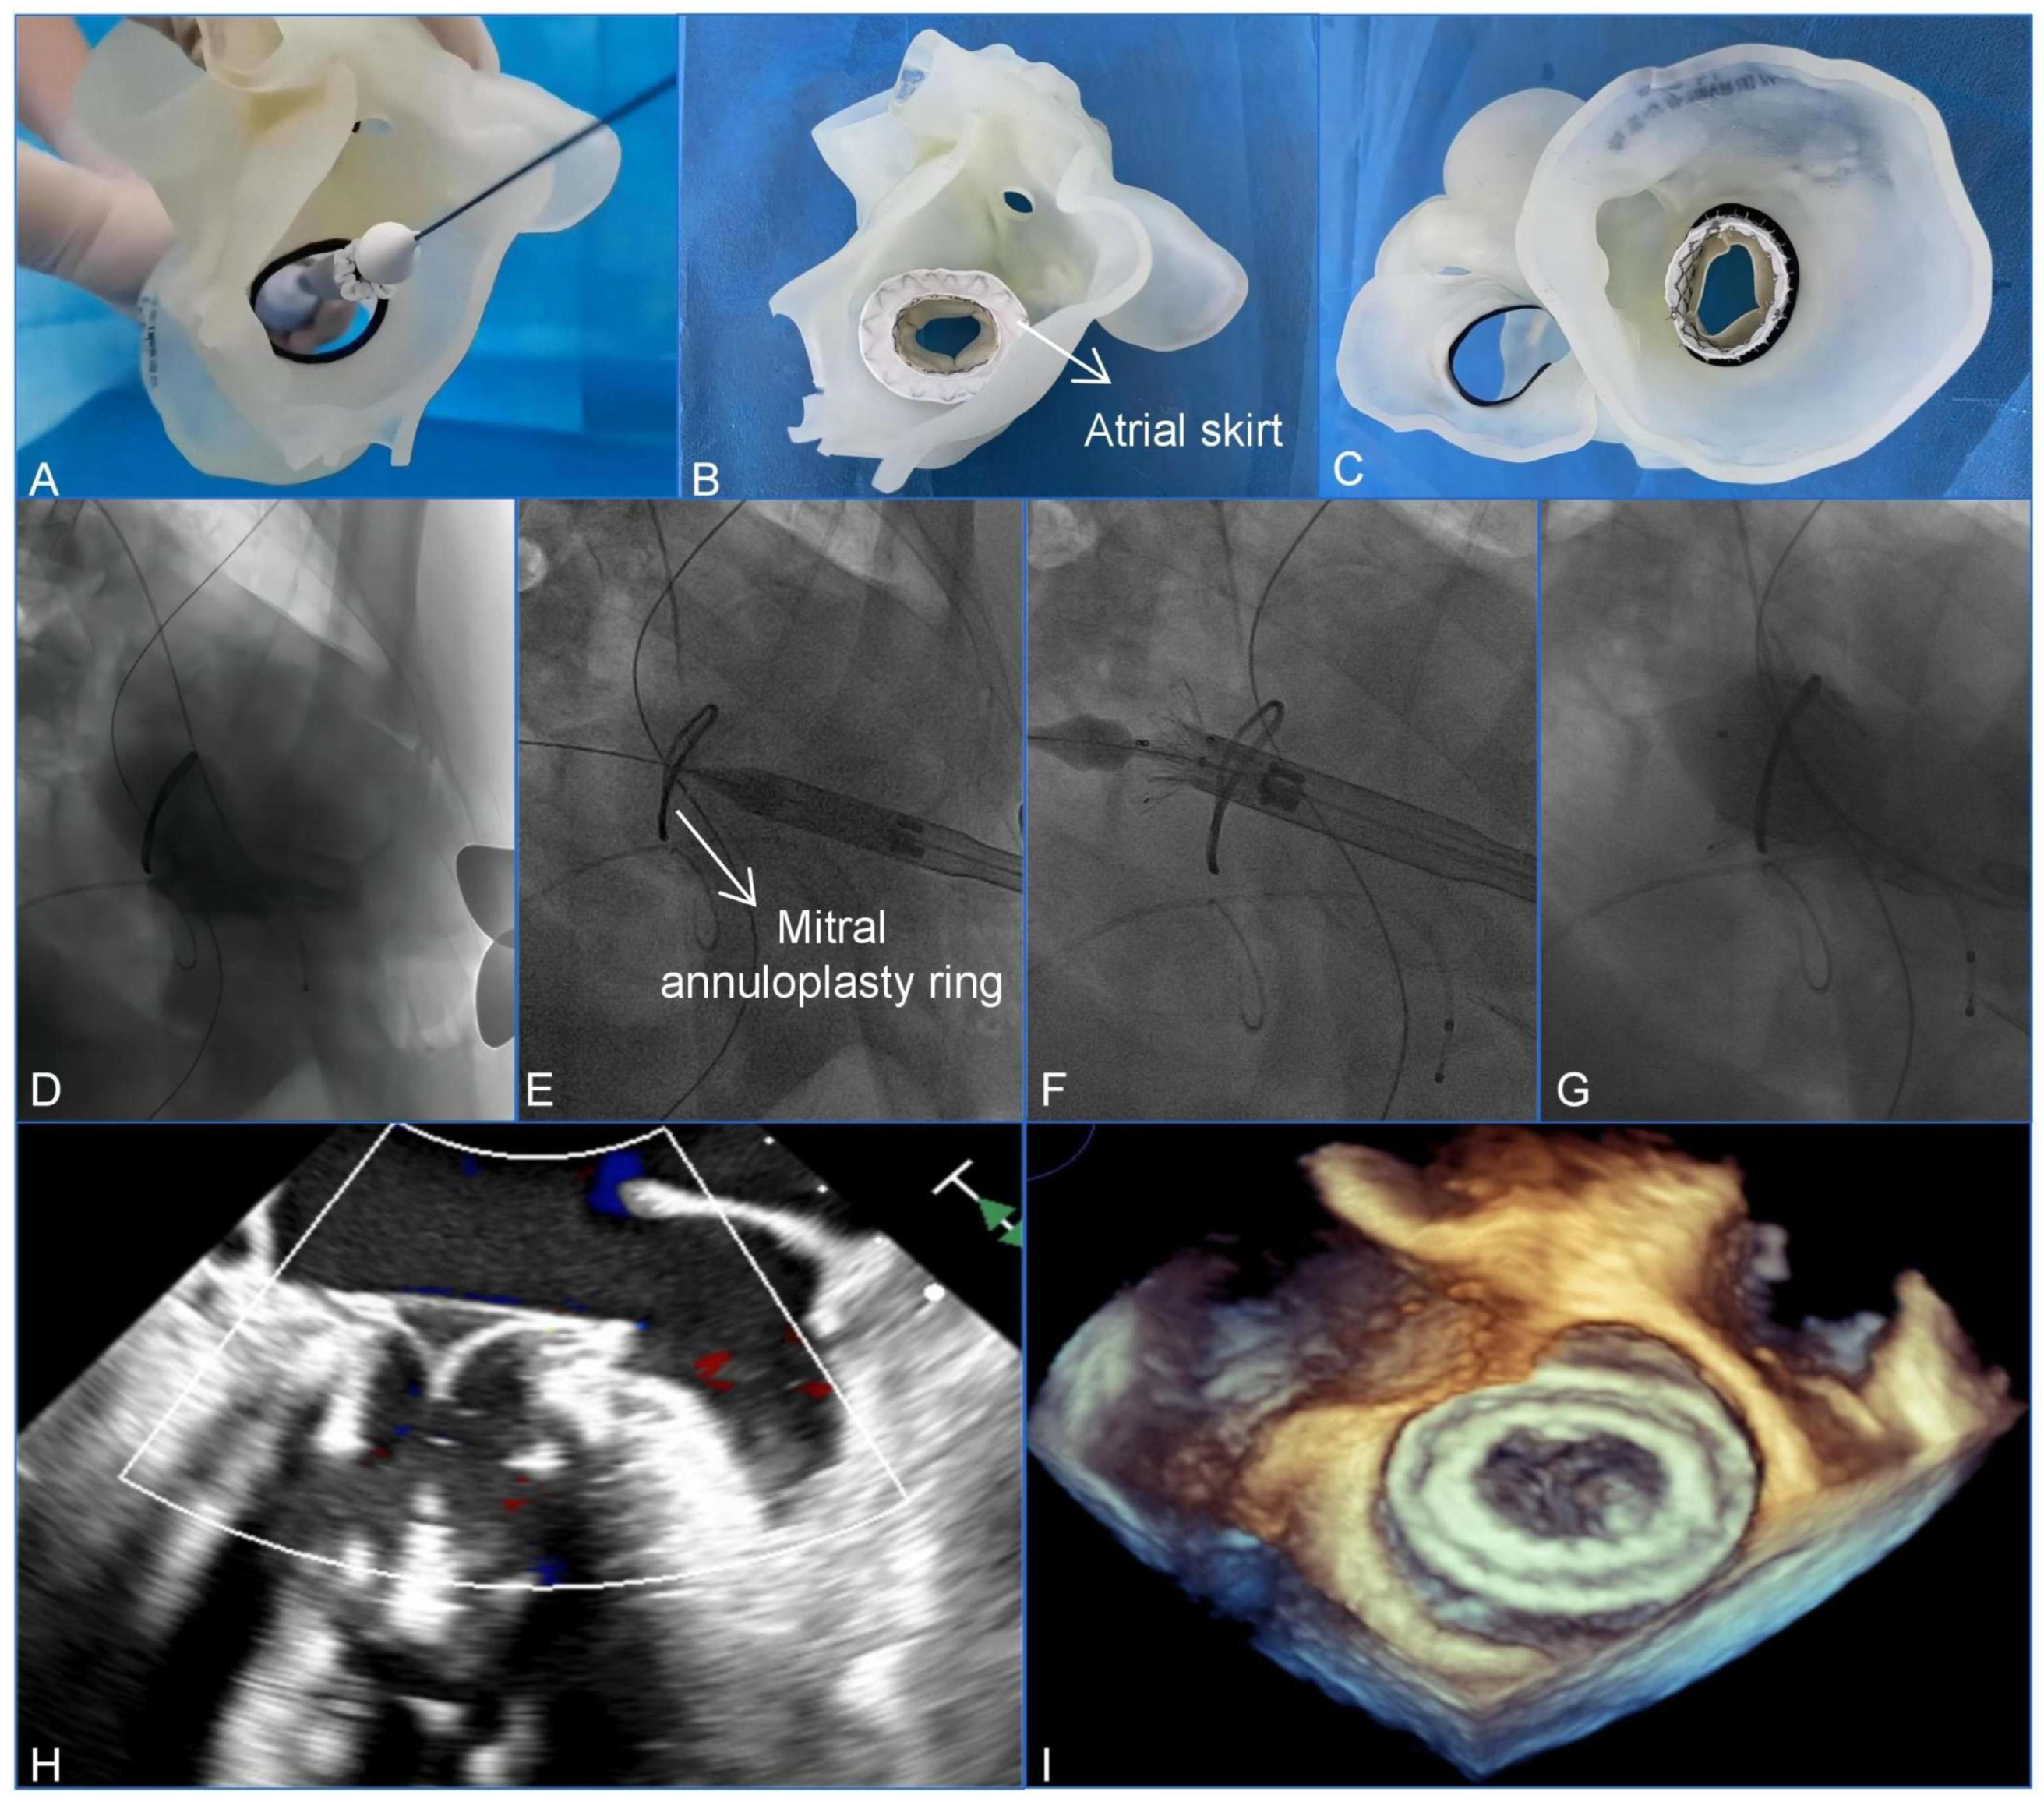

Clinically, 3D printing is essential for assisting with the management of complex cardiac anatomies. Wang et al. utilized a patient-specific 3D-printed model to guide a transcatheter mitral valve-in-ring (TMViR) replacement, which assisted with valve sizing and anticipating intraoperative complications. This study confirms new clinical directions, such as endovascular navigation enabled through the use of 3D-printed models [contribution 8] (Figure 2).

Figure 2.

A preoperative assessment and simulation of the main procedural steps for a transcatheter mitral valve-in-ring replacement on patient-specific 3D-printed models. (A) The adjustment of the coaxiality and the release position. (B,C) The stent was fully unfolded and observed in the left atrial and the ventricular views. (D–G) The main steps of the procedure. (D) Fluoroscopy revealed severe mitral regurgitation. (E) The delivery system was advanced via the transapical approach. (F) The initial release of the stent. (G–I) After the stent was fully released, fluoroscopy and transesophageal echocardiography revealed that the bioprosthesis was in a stable position and functioning well without paravalvular leakage. Reprinted with permission under an open access protocol from Wang et al. [contribution 8].